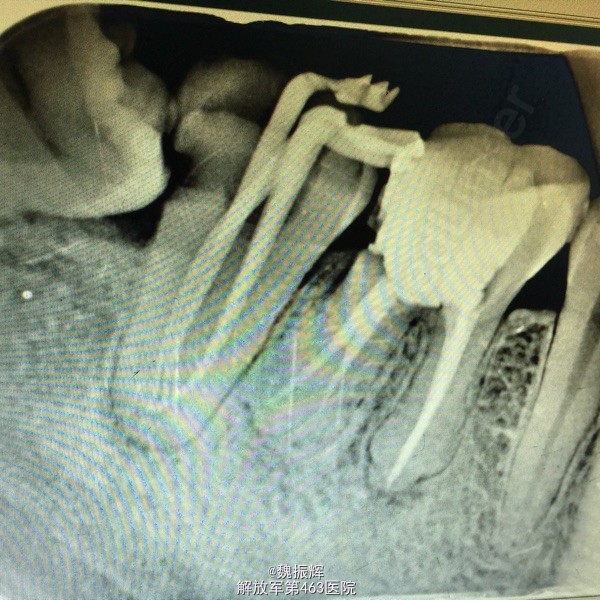

查体:47远中邻面龋坏,探(+),冷(+),叩(-),X线示远中龋坏近髓,48近中阻生,47,48之间食物嵌塞。

诊断:牙髓炎 处理:局麻下,47降牙合,去腐,开髓,揭髓顶冲洗,拔髓,根管疏通测量及机用镍钛器械进行根管预备,次氯酸钠进行根管冲洗,大椎度牙胶尖试尖,进行根管充填。Zoe暂封,观察嵌体修复。择期拔除48。